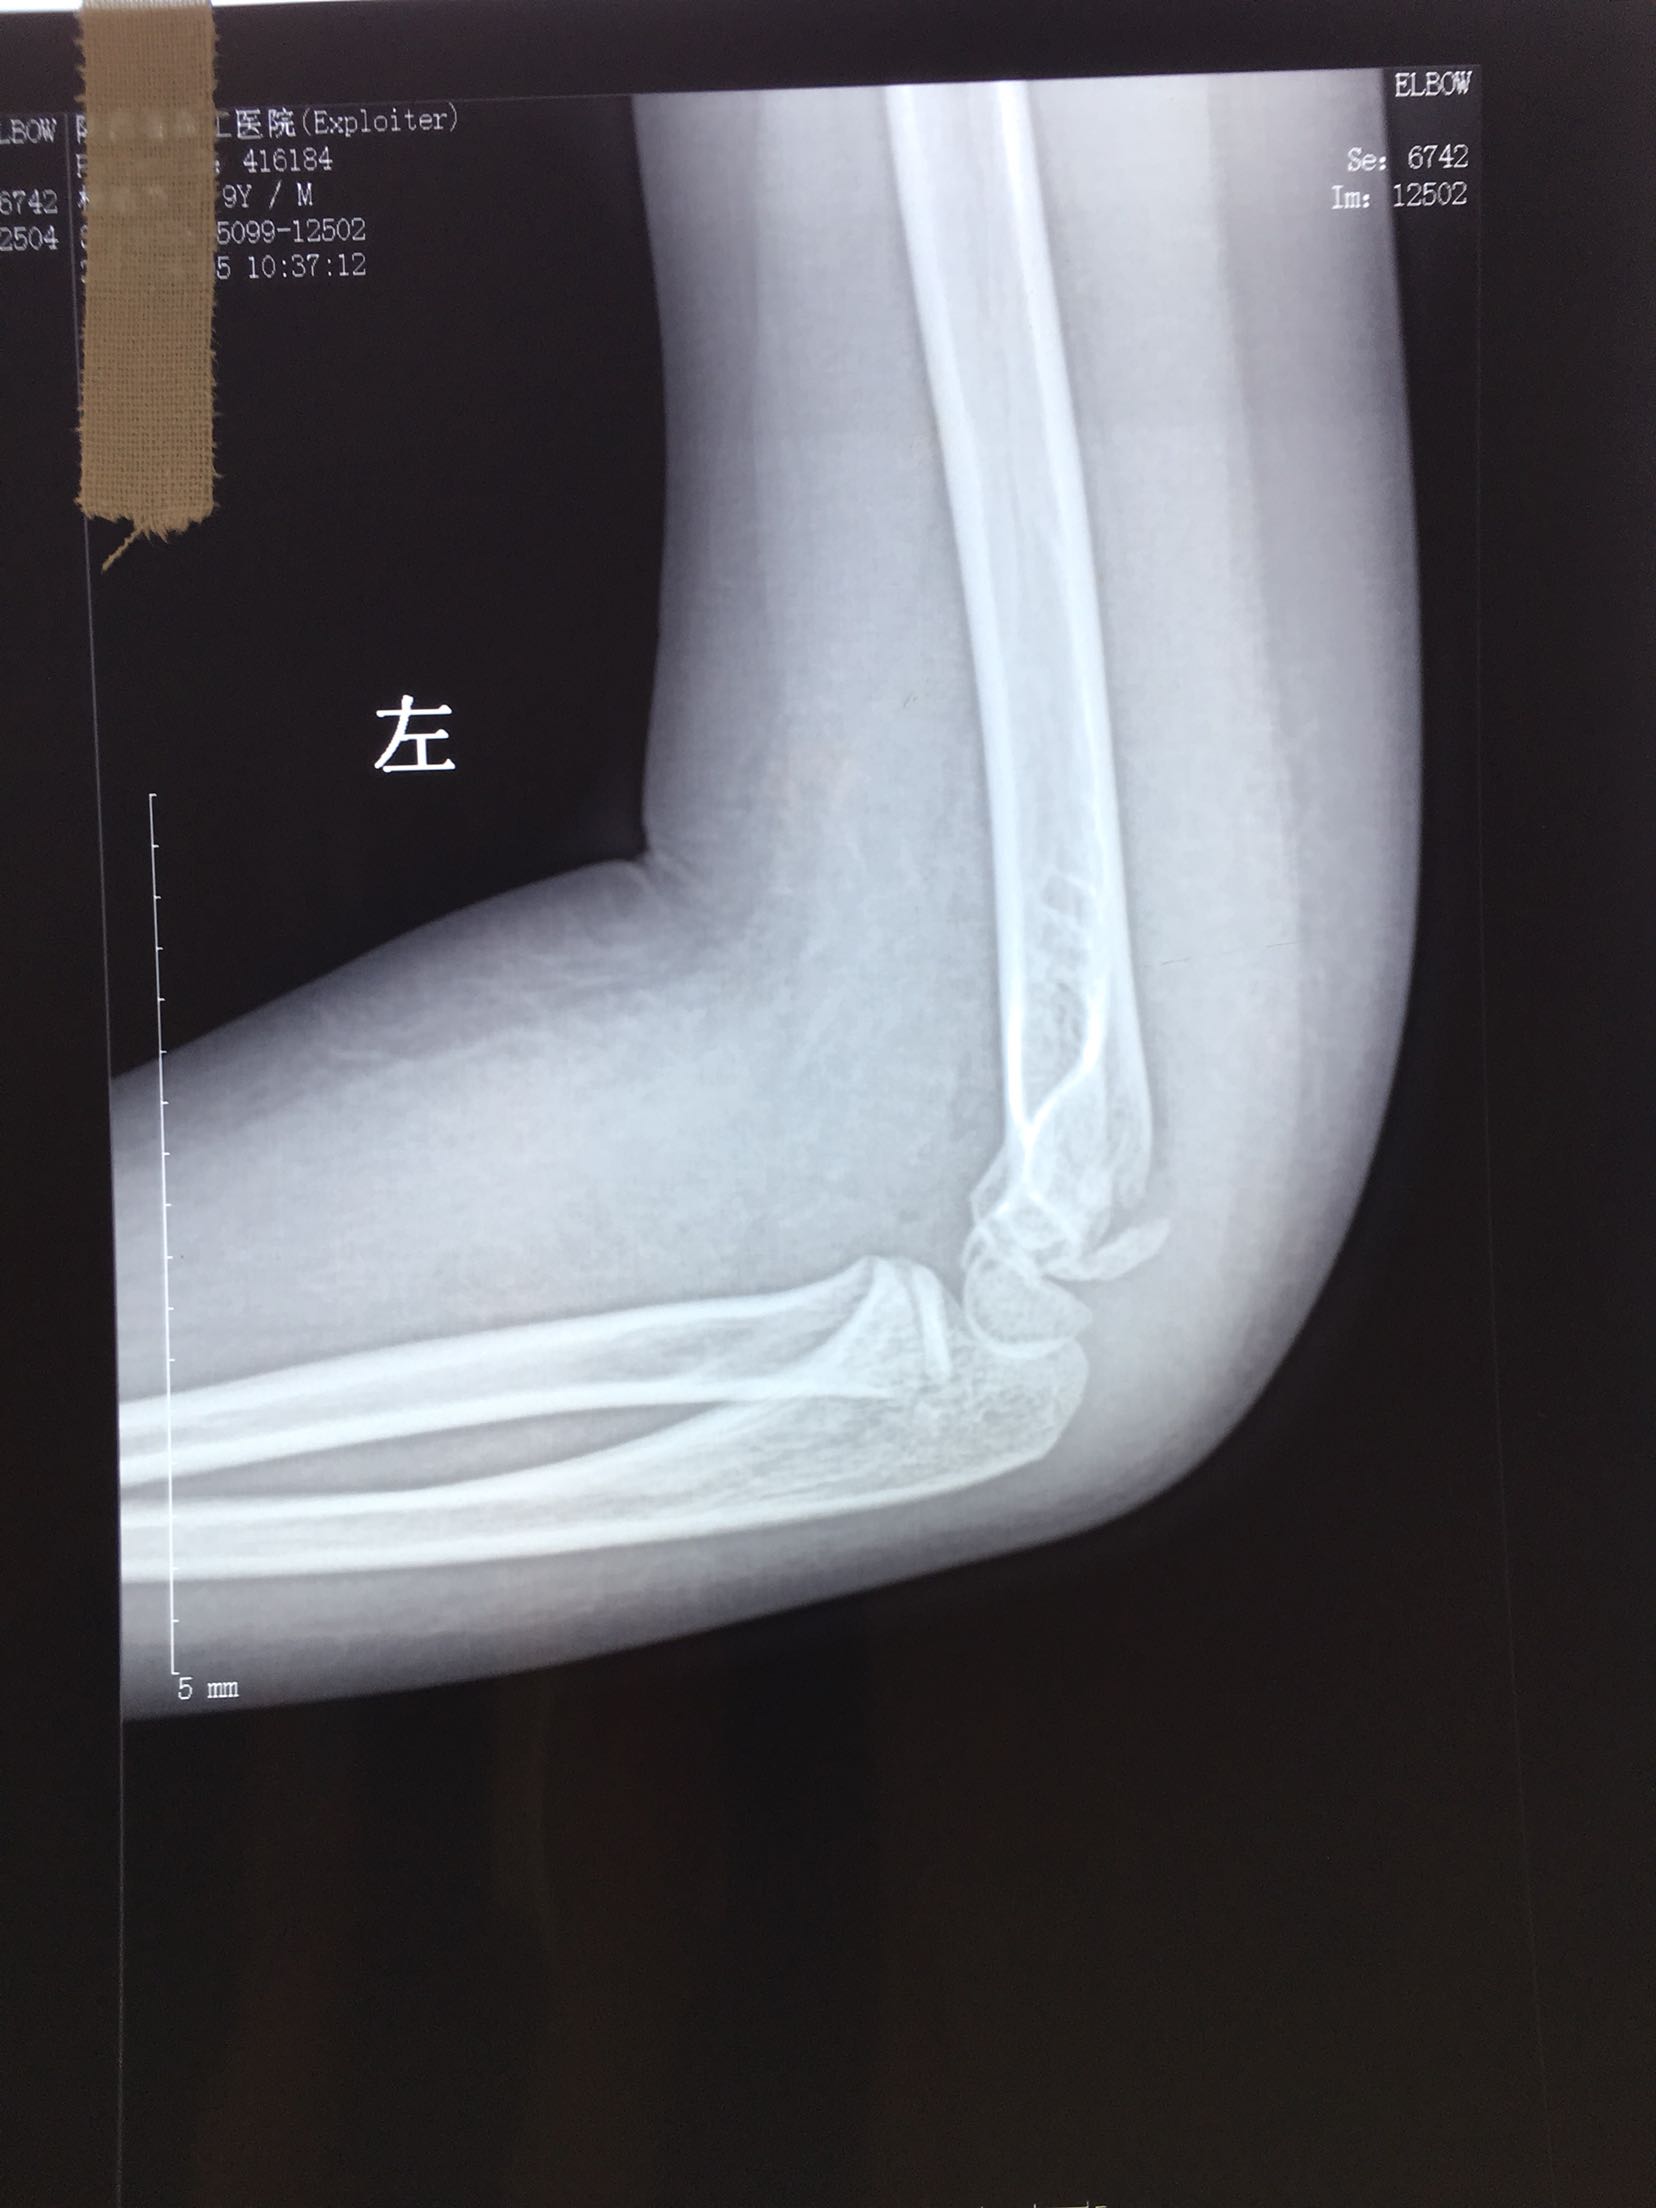

儿童肱骨小头骨折

患儿,男,9岁,摔伤后左肘肿痛,活动受限1天。

左肘部肿胀,压痛明显,肱骨纵叩痛阳性,肘关节活动受限,余未见异常。

完善检查,在臂丛麻醉下行切复内固定术,术后肘关节90°固定2-3周。